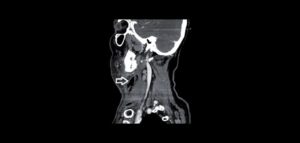

La sialoadenitis secundaria en relación a la sialolitiasis es más frecuente en la glándula submandibular que en otras glándulas, siendo infecciones agudas como también crónicas.